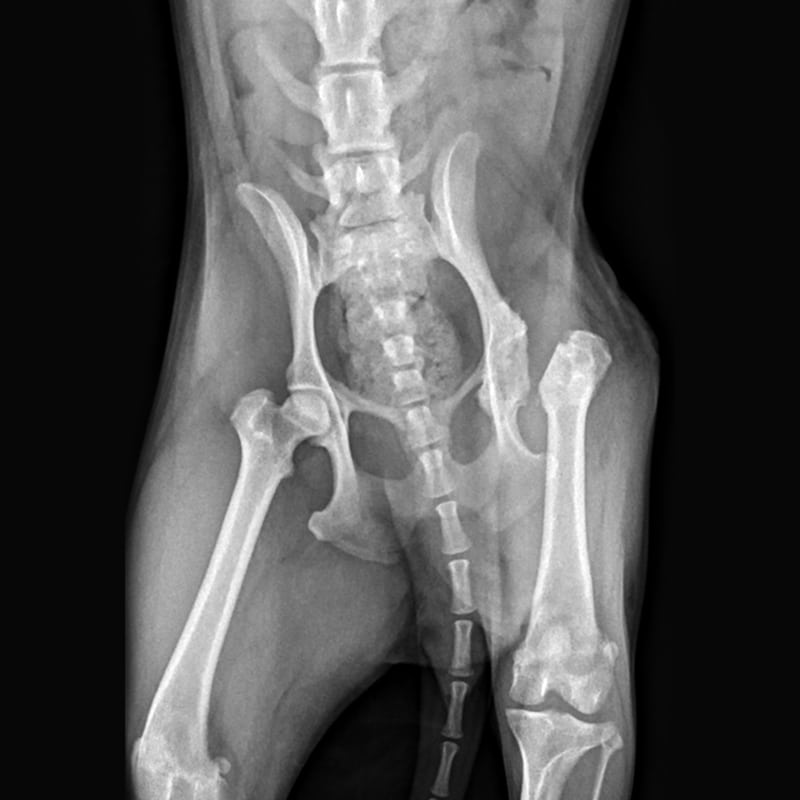

Femoral Head Osteotomies

Surgically removing the head and neck of the femur to alleviate pain and improve mobility in pets who suffer from severe hip joint disease.